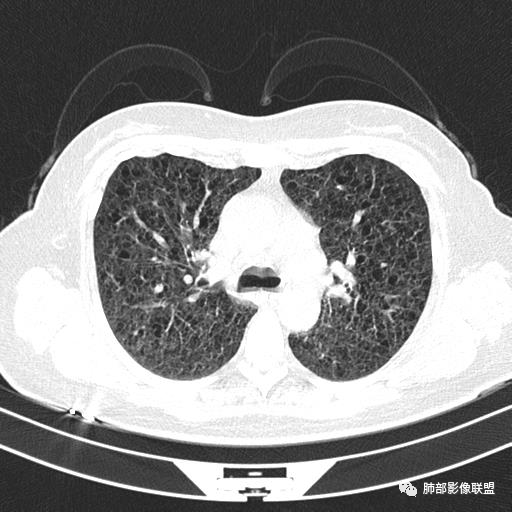

双肺弥漫囊腔,累及肋膈角,囊腔形态相对规则单一。

CT平扫示双肺弥漫分布大小不等囊状薄壁透光区,无内、中、外带分布差异,间质稍示增厚。拟LAM

中年女性育龄期妇女,咳嗽气喘,无吸烟史,有苯吸入史。影像:双肺弥漫均匀小囊腔,无明显分布优势,囊腔形态欠规则,壁薄,部分囊腔边缘血管征,伴双肺弥漫磨玻璃影,无结节,考虑lam,鉴别苯中毒肺损伤,囊腔多有分布优势,小叶中心分布为主,形态规整等

女,46,活动性气喘1年。苯吸入史半年。胸部CT:两肺弥漫囊腔,上至肺尖,下至肋膈角,形态类似小囊腔。考虑:LAM,鉴别LIP,BHD,PLCH等。

双肺弥漫大小不一薄壁含气囊腔,囊间肺组织正常,正常肺背景,肺尖肺底受累;青年女性,气喘,支持LAM

双肺多发大小相近的囊状影,分布趋势趋于一致,中年女性,考虑LAM。部分囊内见血管及分隔影,小叶中心性肺气肿代排

CT表现:双肺弥漫大小不等的薄壁囊腔,囊壁<2mm,外形规则,血管影多位于囊腔周围,囊腔之间肺组织正常,随着疾病进展到晚期,囊腔变大、增多,不可胜数,囊腔可融合成较大的囊,与肺气肿相似,形成间质性肺纤维化。部分病例可出现结节影。